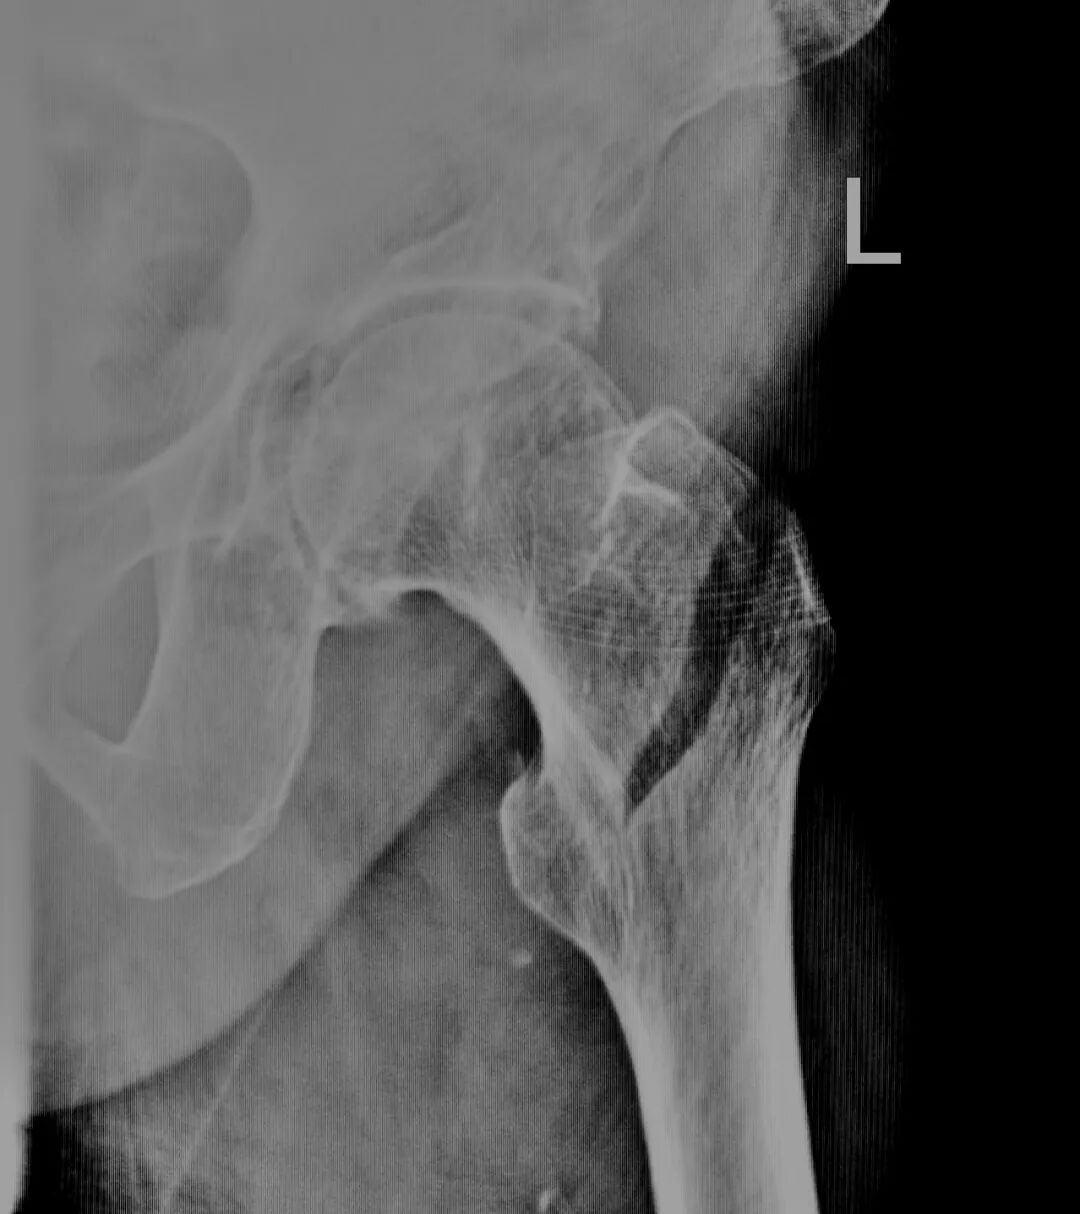

术前,转子间骨折

术后,骨折固定完美

近日,红阳医院外科,在手术室麻醉医师的配合下,为一位96岁高龄的老奶奶进行了左侧股骨转子间手术内固定术。麻醉过程顺利,手术成功。